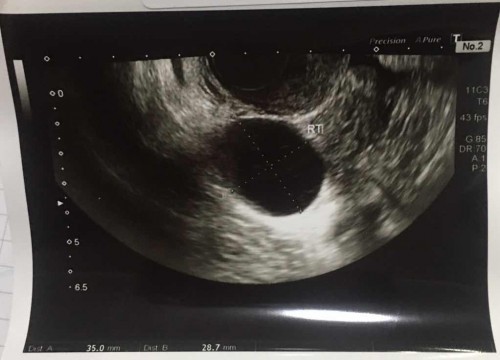

ซาวด์ตั้งครรภ์ครั้งแรกและเจอซีสต์ในรังไข่ข้างขวา ขนาดตามรูปเลยคะ หมอว่าไม่เป็นอันตราย ใครเคยเป็นบ้างคะ#ขอคำแนะนำค่ะ